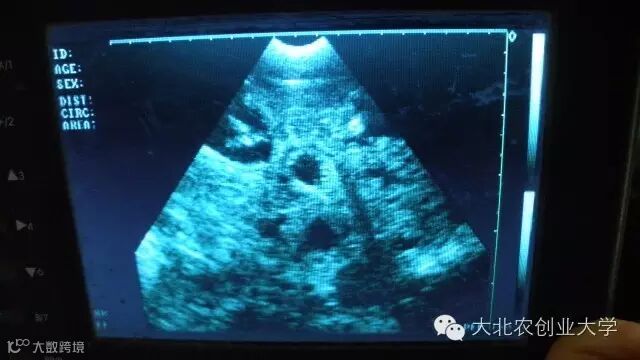

B超检测图片讲解

妊娠50天图像

妊娠70天图像